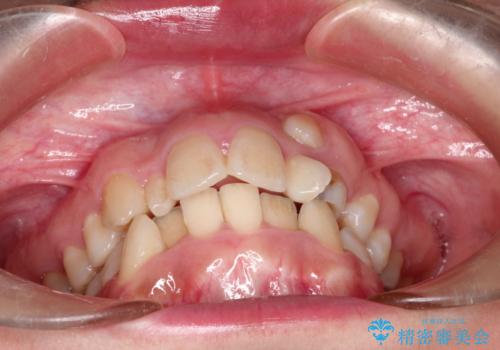

左上の犬歯が通常の位置より、かなり上方にあり、乳歯の残存と前歯のがたつきがありました。

残った乳歯と上下左右の永久歯を1本ずつ抜歯して、ワイヤーにて矯正することとしました。